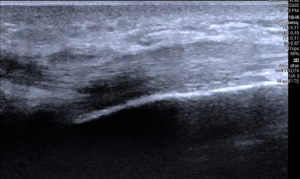

La valoración física y el examen clínico por un médico como la Dra. Vivian Tecú, es de suma importancia y nos provee el diagnóstico, con tests como el de FINKELSTEIN la probabilidad del diagnóstico aumenta. Sin embargo en la actualidad apoyarse de un estudio diagnóstico como la ecografía de muñeca (ultrasonido de imagen) brinda datos y cambios que confirman el diagnóstico como en las imágenes que vemos abajo.